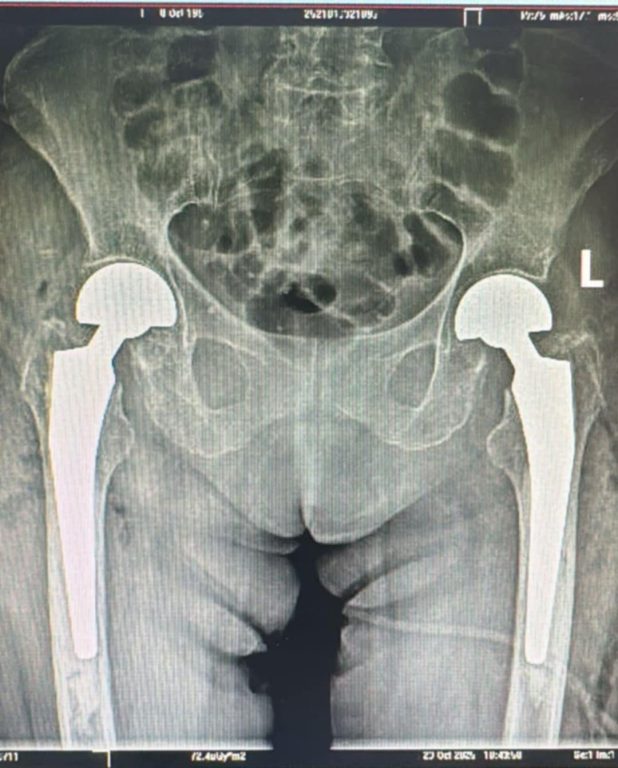

Echipa Secției Ortopedie-Traumatologie a realizat, în premieră pentru spital și pentru județul Sibiu, o intervenție chirurgicală complexă: artroplastie parțială de șold bilateral, efectuată în același timp operator.

Pacienta, în vârstă de 73 de ani, a ajuns în UPU cu dureri intense și imposibilitatea de a se deplasa. Investigațiile au arătat o fractură bilaterală de col femural, o patologie gravă și extrem de rar întâlnită.

După pregătirea preoperatorie, echipa medicală a decis intervenția simultană pe ambele șolduri – o procedură cu un grad ridicat de dificultate.

Operația a fost un succes, iar evoluția pacientei este favorabilă. În prezent, se află în proces de recuperare și se poate deplasa.